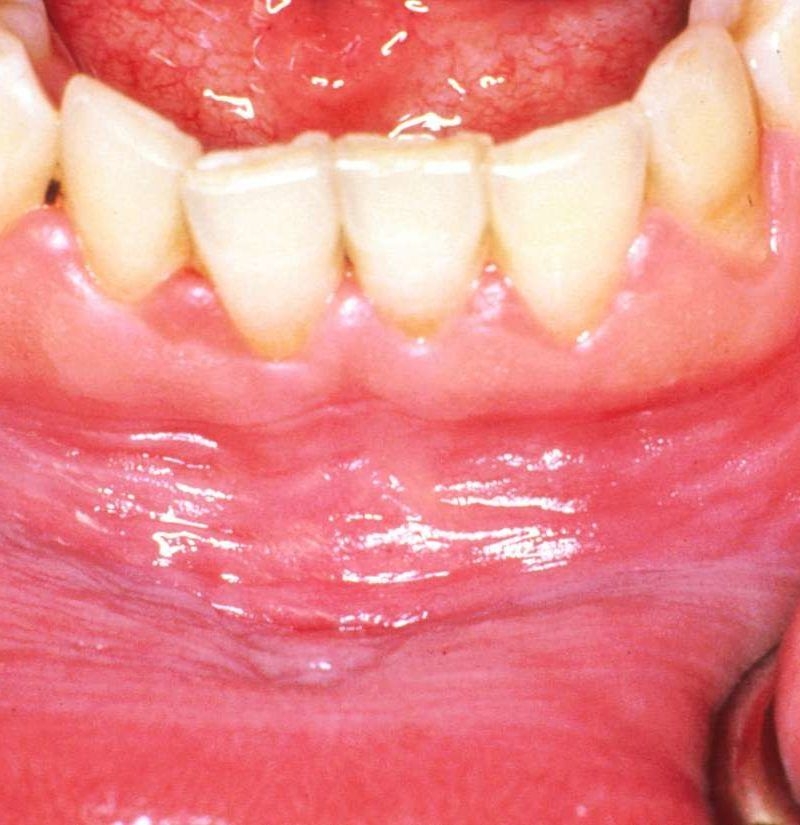

White dots on gums can be caused by a variety of factors, including canker sores, oral thrush, or even oral cancer. Canker sores are small, painful ulcers that can develop on the gums and other areas of the mouth. Oral thrush is a fungal infection that can also cause white patches on the gums. In more severe cases, white dots on gums can be a symptom of oral cancer, which requires immediate medical attention.